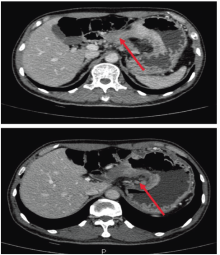

放化疗结束后再次行CT评估治疗效果。此时我们需要明确该如何对胃癌新辅助治疗后的患者进行再评估。

王秋实:RECIST形态学标准是目前国际通用的实体肿瘤评效准则, 但其在胃肠道癌新辅助化疗的应用却遭遇瓶颈。原因在于胃癌原发灶测量的一致性和可重复性差, 不建议作为可测量靶病灶。而肝、肺或淋巴结转移病灶作为靶病灶具有良好的测量一致性和可重复性, 但大大降低可评价患者的数量。也有采取TNM分期变化作为疗效评估的, 但其本质仍为形态学标准, 良恶性征象交叉较多, 导致分期不准。胃肠癌CT和MRI新辅助治疗前后T分期的准确率从60%~90%下降至40%~70%。此外, 功能影像学评价PET-CT的SUV值变化可早期评价新辅助治疗的疗效。MRI弥散加权成像(diffusion-weighted MRI):ADC值与恶性肿瘤疗效相关, 可作为新的预测和随访恶性肿瘤疗效的生物学行为指标。针对该例患者原发病灶受胃腔形态、充盈度影响, 无法准确测量长径和厚度; 病变与胰腺间脂肪界面仍消失, 但无法从影像学角度区别是炎性反应还是肿瘤侵犯。胃周淋巴结明显缩小、强化仍较明显, 无法判断是否仍有活性转移。因此, 对于胃癌新辅助治疗后的疗效评价, 建议多学科讨论。

冯兴宇:采用RECIST 1.1版, 根据该标准, 患者疗效评价为疾病稳定。下一步该如何治疗?